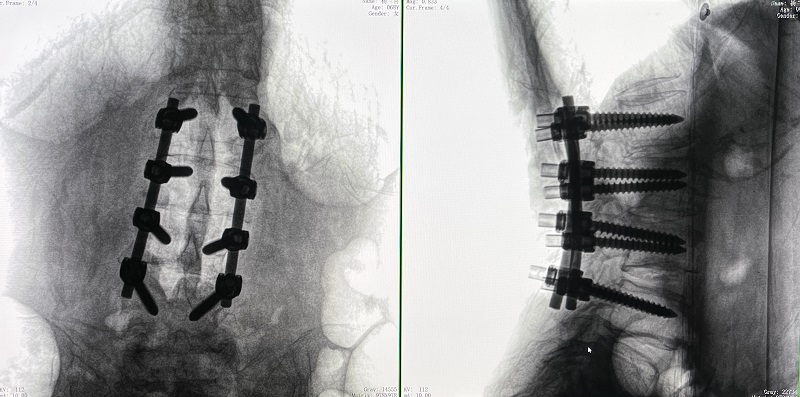

(4)在骨科机器人导航系统辅助下,一次性准确植入8枚椎弓根螺钉。

对于这类复杂脊柱侧弯手术,普爱医疗脊柱外科手术全流程解决方案应对自如,缩短手术时长,在增加手术安全性的同时,提高手术效率,有效改善患者预后情况。

术后图像